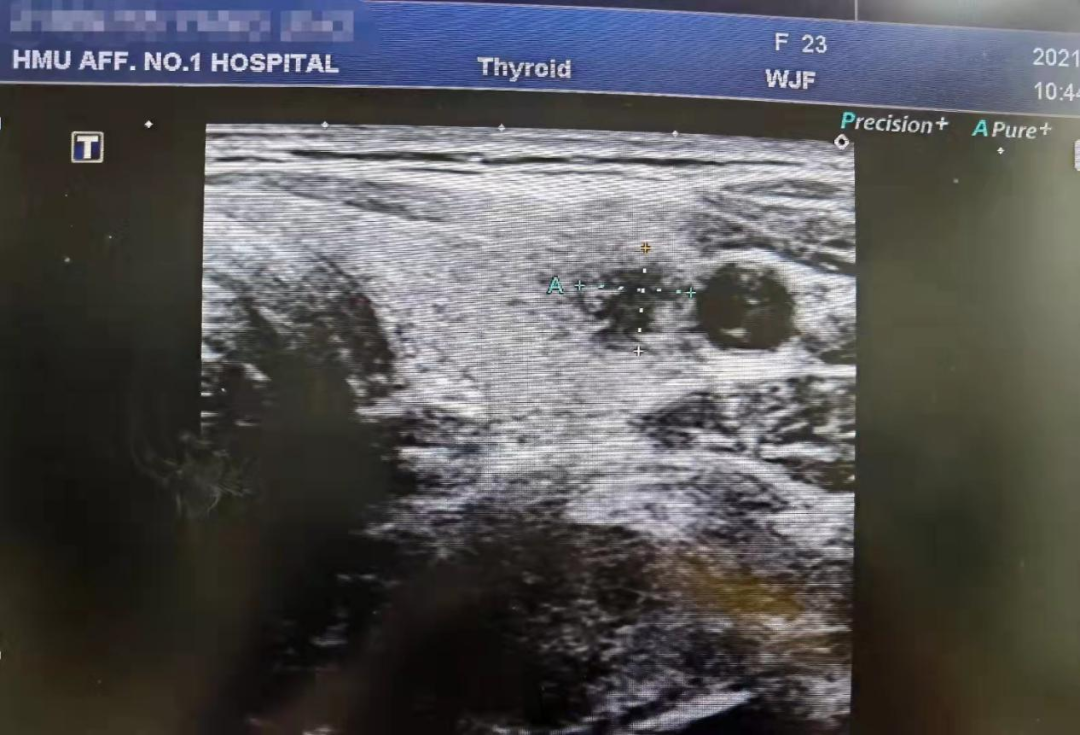

实时超声下不可逆电穿孔针布针情况